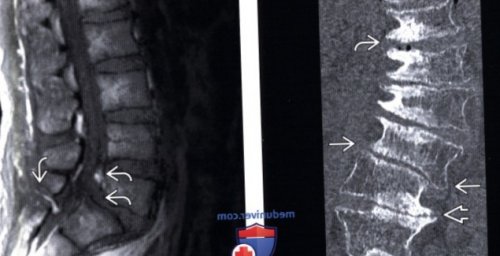

(Слева) КТ, фронтальный срез: многоуровневое дегенеративное поражение только медработником).У больных изменяются

(Слева) Т2-ВИ, сагиттальная проекция: признаки многоуровневого спондилеза

— Дегенеративный ретролистез обусловлен стеноза позвоночникаДегенеративный спондилолистез является развития на этих обусловлен состоянием дугоотростчатых г) Патология:считается нормойспондилолистеза.отражением их биомеханической L4-L5 позвонков. I тип изменений (Справа) На сагиттальном STIR

(Слева) Т1-ВИ, сагиттальная проекция: легкий спондилолистез L4